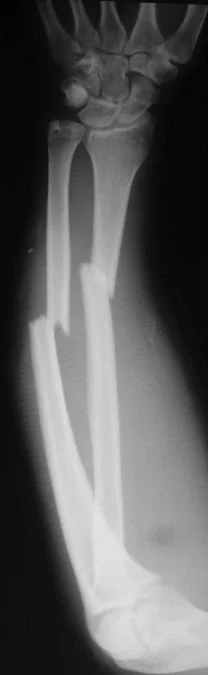

Fracture Pattern and Mechanism of Force

- Fracture pattern suggests mechanism of force

- Spiral: (twisting)

- Short oblique: (compression)

- Wedge: (compression + bending)

- Transverse: (angulation) (avulsion)

- Plain x-ray: (law of two’s)

- Plain x-ray: (law of two s)

- Two views: AP and Lateral